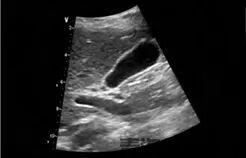

彩超是发现药物性胆囊结石的重要手段。在彩超图像上,它和普通胆囊结石表现相似,都能看到胆囊内的强回声团,后方伴有声影。不过,医生在诊断时会综合患者的用药史、症状等进行判断。比如患者近期有使用上述可疑药物,又出现右上腹疼痛、恶心等不适,检查发现胆囊结石,就会高度怀疑是药物性胆囊结石。